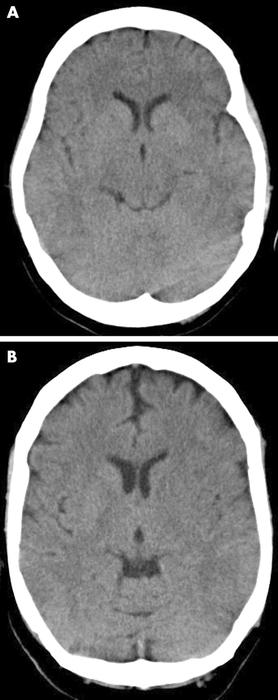

Two examples of early ischaemic changes on CT in sub-three hour ischaemic stroke. (A) Acute left middle cerebral artery (MCA) ischaemia with loss of insular ribbon, and hypodensity of tail of lentiform nucleus. (B) Similar changes in a different patient, with hypodensity of entire lentiform nucleus, some hemispheric sulcal effacement, and compression of lateral ventricle caused by hypodensity of caudate head

Muir KW et al. Neurology, Neurosurgery & Psychiatry 2005; 76: iii19-iii28; used with permission